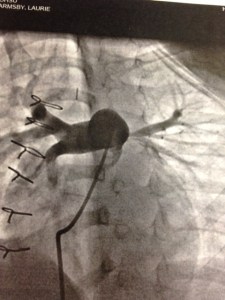

When I was matched with Cheng Chun (Iris), there was an added complication because I was not familiar with her specific congenital heart defect. My adoption agency gave me a list of specialists that regularly review medical files, and I also reached out to my local contacts. Over the next 72 hours, I had lengthy conversations with four doctors, and received opinions that teetered between unfavorable, and frightening. I had a huge pit in my stomach as I tried to process the severity of Cheng Chun’s condition, the complexity and risks of surgery, her long-term prognosis, and the impact to Solana. I had a few more phone calls to make, and next on my list was Dr. Mark Reller, head of cardiology at Doernbecher. I told Dr. Reller about the opinions I received, and my fears. Dr. Reller’s opinion was dramatically different from the others, and he optimistically said, “You need to call Dr. Stephen Langley. He has successfully performed this surgery with great outcomes.”

Dr. Langley and I connected less than an hour before I needed to give an answer to my adoption agency. Dr. Langley walked me through the surgery, recovery, short-term challenges, and long-term prognosis. His next statement is forever imprinted in my mind; “If you adopt this little girl and I perform her surgery, I will do everything in my medical power to give her the best chance for a long, healthy life.” I still can’t say, or write, those words without tearing up. I had only met Dr. Langley once briefly, but I was well aware of his reputation and integrity, and I knew he wouldn’t make that statement unless he was confident that he could fulfill it. So I believed him. With every part of my being .. I believed him.

On January 28th, 2013, Solana and I were united with Iris in Hefei, China. In the coming weeks I learned that Iris’ condition was even more serious because of the malformation of her trachea, but Dr. Langley had planted a seed of trust, and although I was scared, I knew Iris was in the best hands possible. On June 28th, 2013 the promise within Dr. Langley’s words was fulfilled as he and Dr. Michael Rutter (the amazing otolaryngologist from Cincinnati Children’s Hospital) worked side by side, seamlessly, to repair Iris’ heart and reconstruct her trachea.